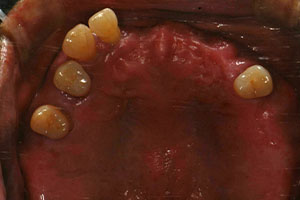

치료증례 전후사진

Before & After